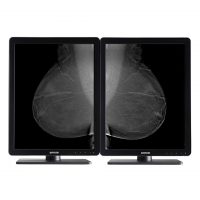

Медицинский монитор — это монитор, который отвечает высоким требованиям к медицинской визуализации в радиологии и маммографии. Он используется рентгенологами для просмотра диагностических изображений, таких как рентгеновские снимки, данные магнитно-резонансных исследований и компьютерной томографии и многое другое. Диагностические дисплеи поставляются со специальными средствами и технологиями, которые помогают рентгенологам быстро и точно поставить диагноз.

Профессиональный медицинский монитор Jusha обладает высоким разрешением, высокой яркостью и 16-битными оттенками серого (уровень 65 536), встроенным DICOM стандарт LUT, обеспечивает требовательный клинический диагноз, как: PACS, цифровая маммография CR, DR и другие радиационные систем